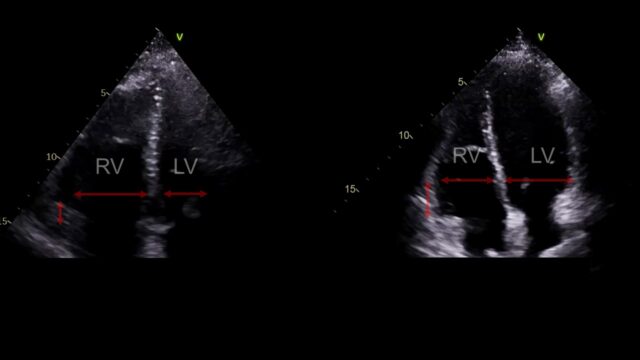

These images are all from a young female with high risk PE with pre and post lysis images. In a revolution of AI assited imaging they now come with added labels…

This is PSSAX view. In a life threatening PE the RV enlarges, the right sided pressures rise and the interventricular septum loses its roundness and becomes flat. This is the D sign you might here of. Like a capital D tilted over slightly.

The apical 4 chamber view. The RV should be smaller than the LV, if it’s a lot bigger something is wrong. This view also allows us to look at something called TAPSE basically how much does this little nubbin at the tricuspid valve move up and down. If it moves up and down loads that’s good, if only a little that’s bad.

You can measure lots of other things and as an echo geek I like to do so but in all honesty in this scenario I am not convinced they add anything over what I’ve just shown you